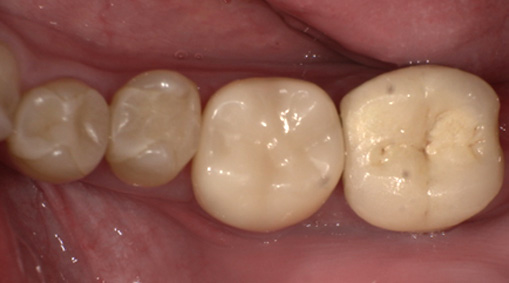

術前・術後の比較

| 術前 | 術後 |

|---|---|

![]() |